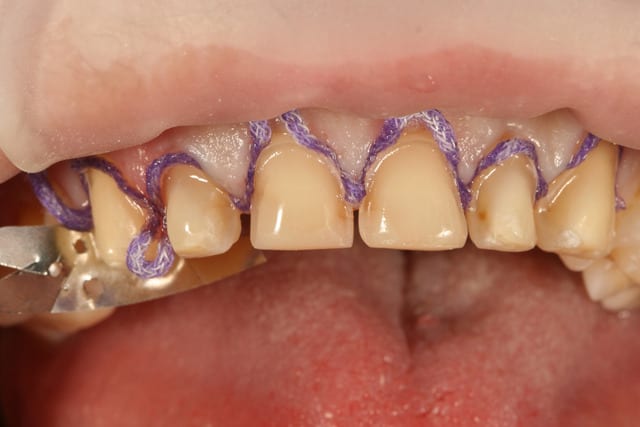

10 retraction jj3ujj - Eugenol

je n'ai rentré le fil qu'aux endroits ou j'étais juxta ou très peu supra

quand à savoir pourquoi je suis juxta à certains endroits et supra à d'autres, je dois avouer que je sais pas trop, j'ai du me dire qu'il fallait descendre un peu en interdentaire parce que les dents étaient assez écartées et que ça permettrait au prothésiste de me faire un plus joli profil d'emergence à ces endroits.

je préfère le fil dans les cas avec plusieurs préparations dans ce style, parce qu'on peut mettre un seul fil et tout tirer d'un coup en injectant derrière